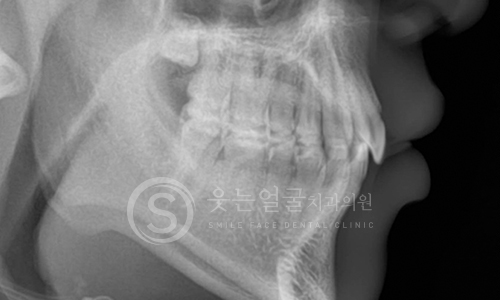

치과의사를 가르치는

강혁권 원장의 임플란트 노하우

미국 NYU 출신으로 임상 경험과 교육 경력을 겸비한

강혁권 원장의 전문 노하우로,

단순 시술이 아닌

과학적이고 체계적인 임플란트 치료를 제공합니다.